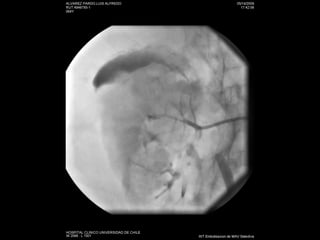

Angiografía

Stent y plastias de estenosis

Estudio No invasivo:AngioTC Doppler Angio RM: esclerosis sistémica nefrogénica Invasivo: angiografía

Stent y plastiasde estenosis